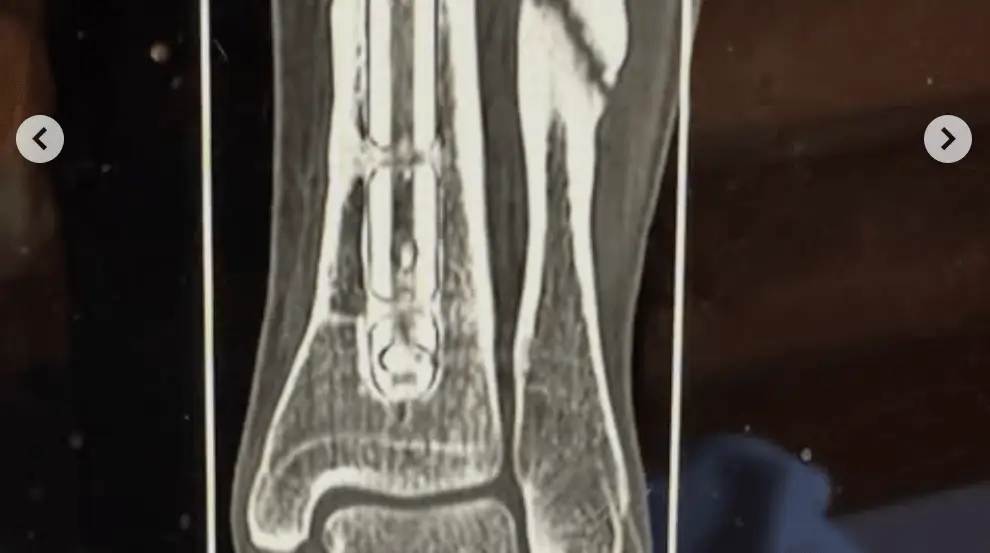

– Jag blev chockad när jag såg röntgenbilden, säger hon.

– Jag blev chockad när jag såg röntgenbilden, säger Huber.

Nu har Lara Huber både skruvar och plattor inopererade i vadbenet.